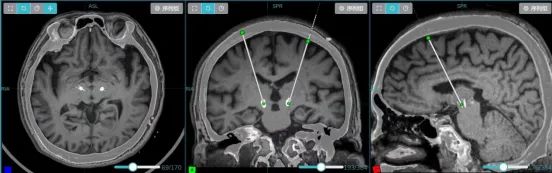

▲ 薄层MRI和CT融合重建 ,显示电极完美精准植入

术后复查CT与术前规划影像融合比对显示,DBS电极植入位置与双靶点完全吻合,手术精准度达到预期。患者生命体征平稳,无出血、感染等并发症,肢体活动如常,微毁损效应显现,肢体僵硬缓解。